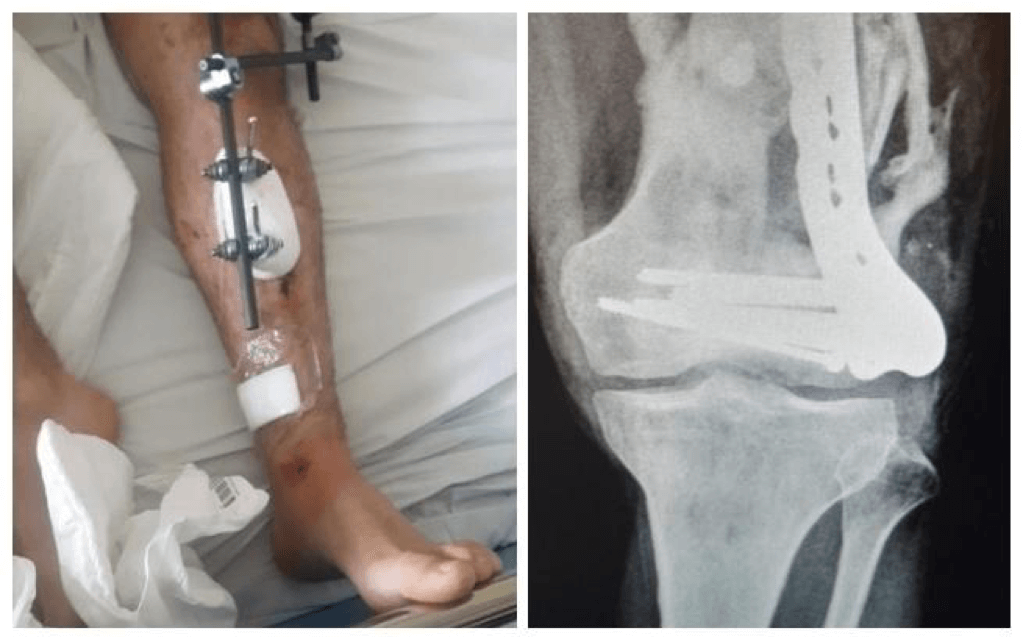

Niedawno dowiedziałem się o konieczności przeprowadzenia operacji (alloplastyki całkowitej stawu kolanowego) wstawienia endoprotezy. Przez wypadek cały staw jest zdeformowany, noga jest krzywa i krótsza o 3 cm co skutkuje bardzo ograniczonymi ruchami w kolanie i nieustannie odczuwam ogromny ból podczas poruszania. Potrzebna jest operacja polegająca na usunięciu zdeformowanego stawu, wyprostowaniu i wydłużeniu kończyny dzięki czemu będę mógł się swobodnie poruszać bez bólu, a co za tym idzie odzyskać choć trochę sprawności .